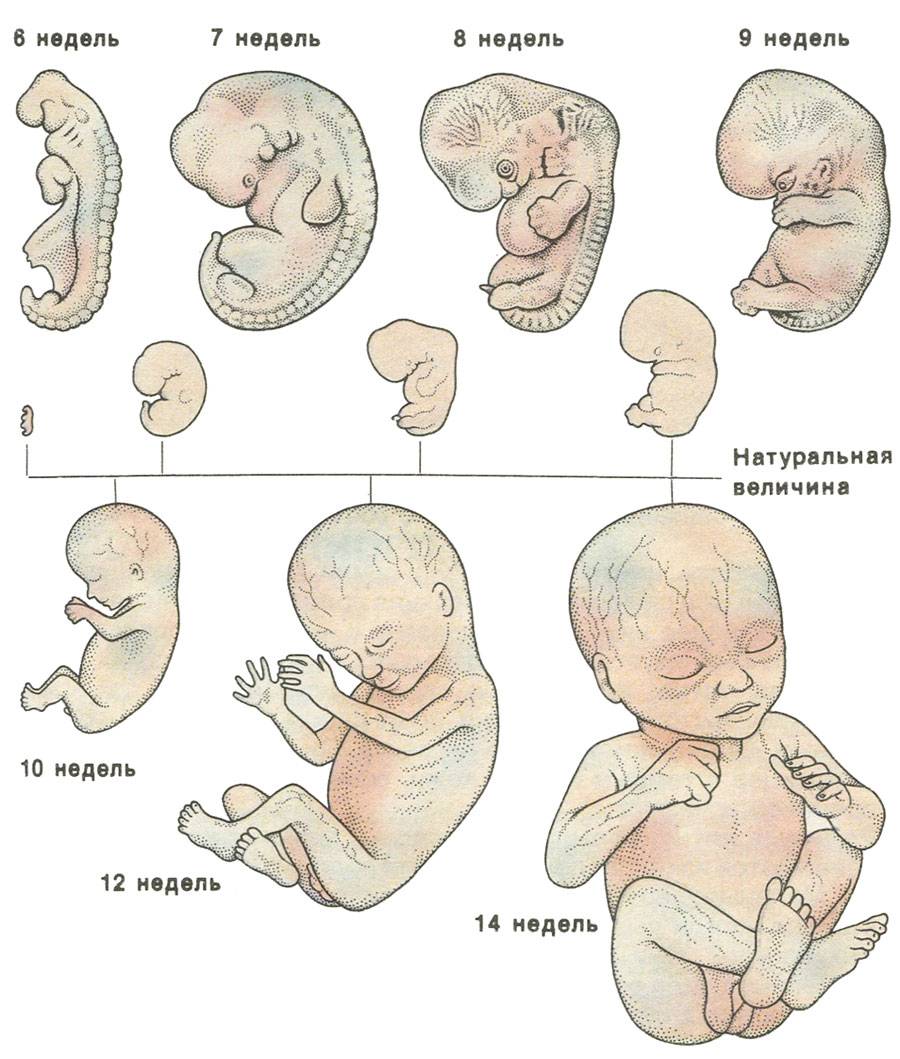

Развитие эмбриона: Что происходит на 3 неделе беременности